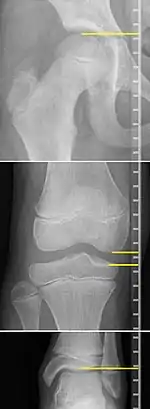

X-rays for leg length measurement.

Unequal leg length in children is frequently first suspected by parents noticing a limp that appears to be getting worse.[3] The standard workup in children is a thorough physical examination, including observing the child while walking and running.[3] Also, at least in United States, standard workup in children also includes X-rays to quantify actual length of the bones of the legs.[3]

On X-rays, there is generally measurement of both the femur and the tibia, as well as both combined.[4] Various measuring points for these have been suggested, but a functional method is to measure the distances between joint surfaces:[4]

• Femur length: The superior aspect of the femoral head and the distal portion of the medial femoral condyle.

• Tibial length: The medial tibial plateau and the tibial plafond

Clinical measurement of leg length conventionally uses the distance from the anterior superior iliac spine to the medial malleolus.[9] Projectional radiographic measurements of leg length have two main variants:[10]

• Teleroentgenogram, which projects the entirety of both legs at the same time.

• Orthoroentgenogram, which takes separate images of the hip, knee and ankle.

On X-rays, the length of the lower limb can be measured from the proximal end of femoral head to the center of the plafond of the distal tibia.[11]